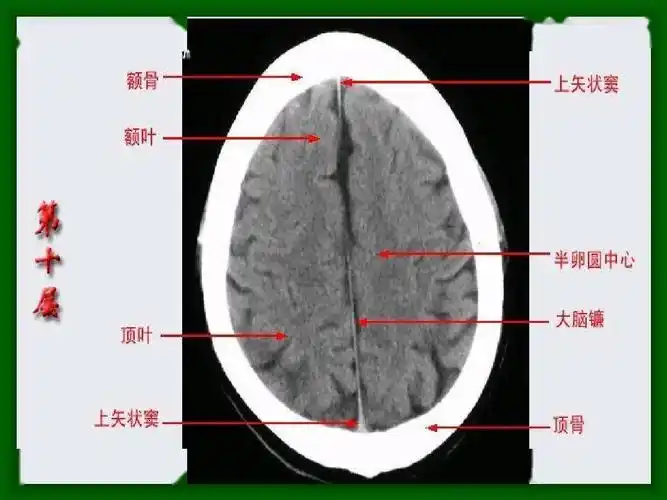

头颅ct 解剖图谱,人手一份